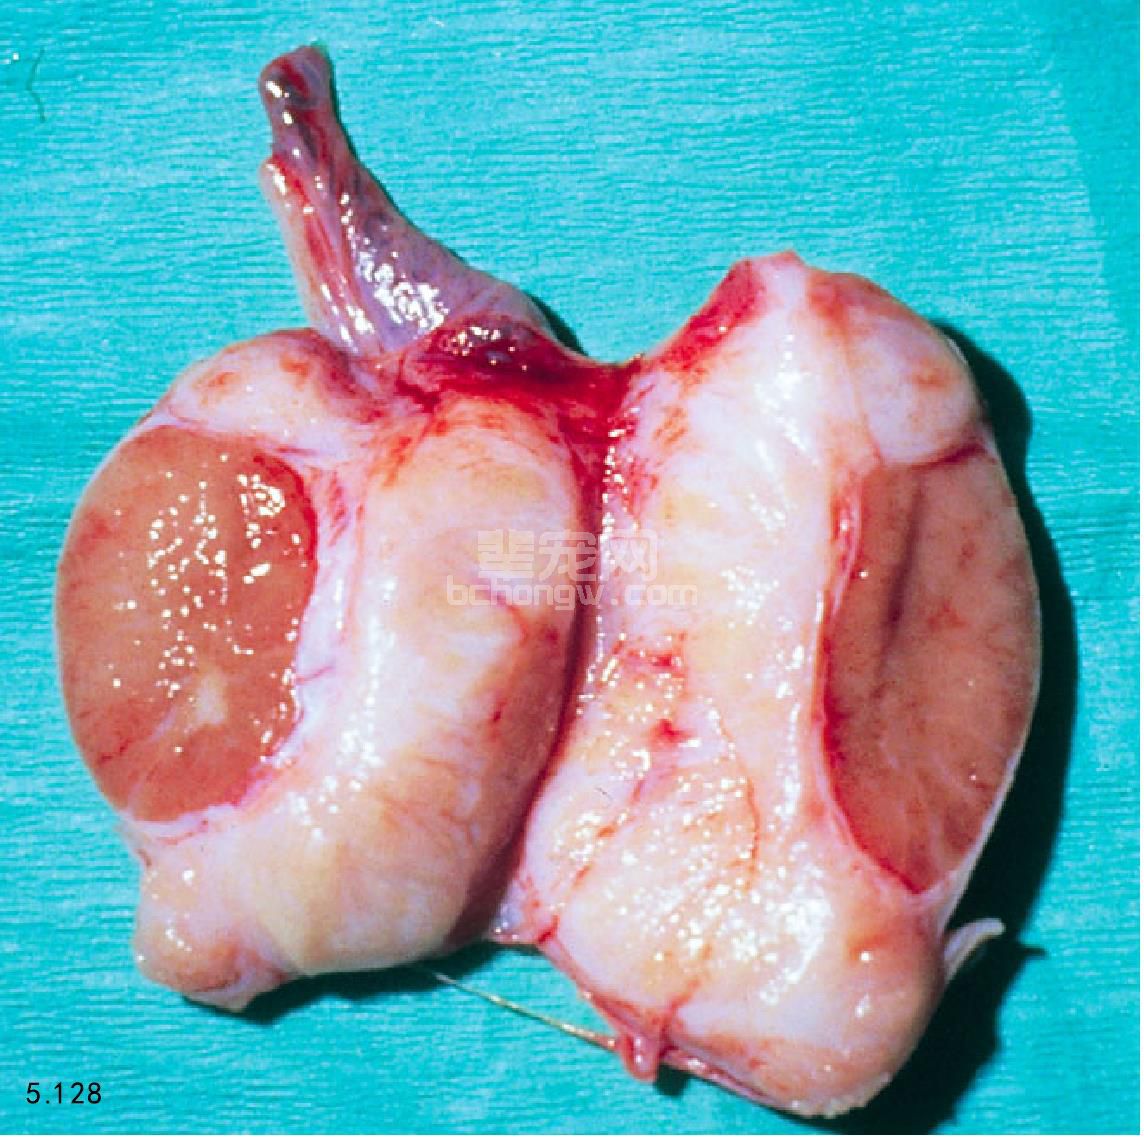

临床症状 阴囊疼痛、发炎、红肿,触诊结实,附睾也可能疼痛(图5.128)。全身性感染会出现发烧和昏 睡。患有附睾炎的犬会出现生育能力降低。

图5.128 严重的睾丸炎引起明显的肿胀和附睾闭塞,以及其后的睾丸实质丢失。